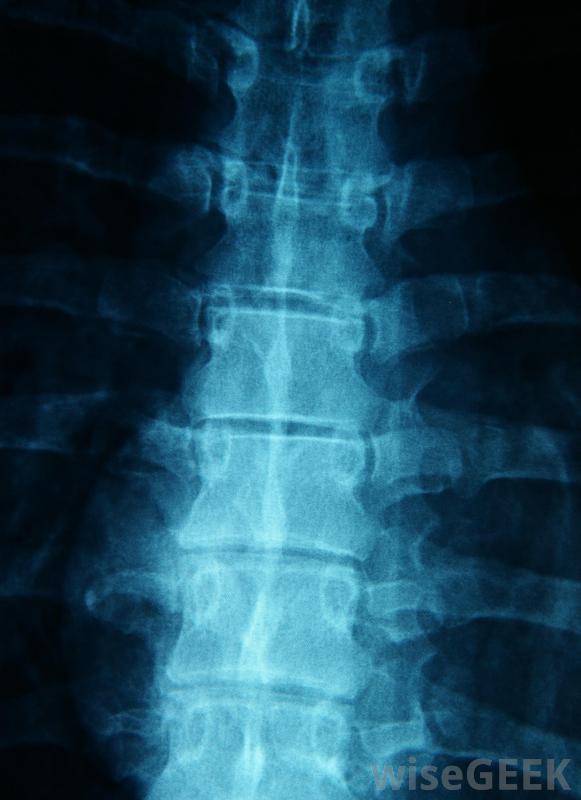

大多数脊椎指压师都会使用X光检查脊柱的总体健康状况脊椎指压疗法对于那些寻求减轻疼痛和纠正由坐骨神经痛引起的问题的人来说是一个很好的选择。脊椎指压师可以在不咨询的情况下诊断和评估坐骨神经痛骨科医生,他们对这种情况的治疗就像对待任何其他由脊柱错位引起的问题一样:治疗过程是基于定期调整脊柱。然后椎骨将重新排列并减压,使脊柱周围的肌肉正常工作,最终减少挤压脊柱的肌肉的张力坐骨神经。总的目标是减轻神经的挤压,消除周围肌肉的过度压力。

某些类型的按摩可能对坐骨神经痛的治疗有用坐骨神经是人体最大的神经之一,这也是坐骨神经痛如此痛苦的原因之一,有时需要多次按摩治疗才能获得缓解。在决定是否尝试脊椎按摩治疗坐骨神经痛时,个人应意识到脊椎指压师喜欢找到调整患者脊柱前的问题。大多数脊椎指压师使用X射线或磁共振成像(MRI)技术来检查脊柱的曲线、组成和一般健康状况。考虑到脊椎按摩的自然、无创、非手术方法,它可以通过一两次探视来确定问题所在和正确的治疗过程。脊椎按摩的实践中心是脊椎的调整和调整,然而,许多脊医在治疗坐骨神经痛时使用电刺激设备来促进愈合过程。电刺激对坐骨神经痛的治疗尤其有效,因为它可以减少肌肉痉挛、神经刺激和炎症。一些脊医在使用脊椎按摩疗法时也会与按摩治疗师合作对于坐骨神经痛的治疗。这种辅助疗法有助于靶向肌肉更快地愈合。坐骨神经痛是一种常见病。人们是否可以通过脊椎按摩治疗坐骨神经痛的问题一直在争论医学界的不同团体。虽然这场争论仍未解决,但成千上万的人,特别是孕妇,已经寻求脊椎按摩疗法来解决他们的坐骨神经痛问题